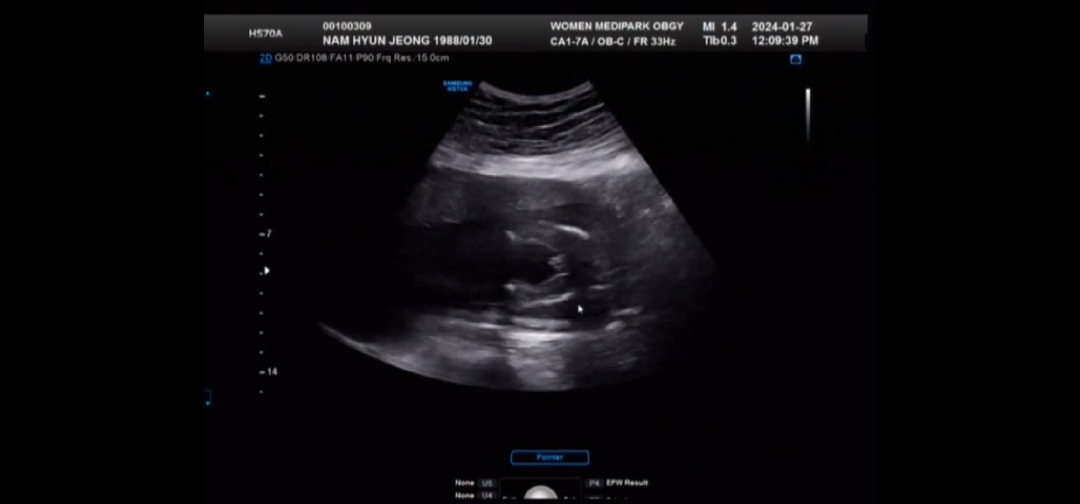

성별좀 봐주세용

19주차 인데 성별잘보시는 맘들! 어때보이시나용?

아들이네용 축하해용😍😍

아들 빼박이시네요!!

왕자님 아닐까요~~? 저는 21주차인데 딸이라서 다리사이가 매끈해요!